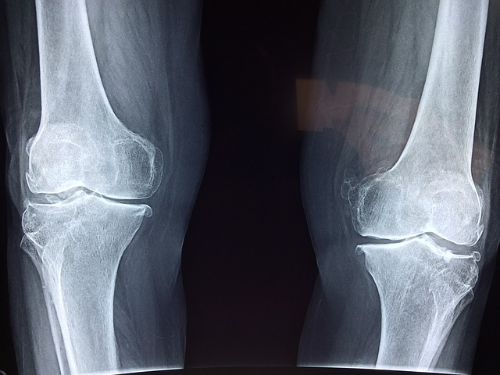

무릎에서 소리가 나는 다른 경우로는 ‘관절염’이 있습니다. 관절염은 무릎 관절의 연골이 마모되거나 손상되면서 관절 간의 마찰이 증가하고, 염증이 발생하는 질환인데요. 관절염이 있는 경우에는 무릎에서 딱딱하거나 사각사각하는 소리가 날 수 있으며, 소리와 함께 통증이 동반되고, 운동 시나 날씨 변화 시에 증상이 악화될 수 있다고 합니다. 관절염의 종류로는 ‘퇴행성 관절염’, ‘박리성 골연골염’, ‘류마티스 관절염’ 등이 있습니다.

또 다른 경우로는 ‘연골판 파열’이 있습니다. 연골판은 반월상 모양의 연골로, 무릎 관절의 충격을 흡수하고 안정성을 유지하는 역할을 하는 기관인데요. 연골판이 파열되면, 무릎에서 삐걱거리거나 걸리는 소리가 날 수 있으며, 통증과 부종이 생기고, 무릎을 자유롭게 움직이는데 불편함이 생길 수 있다고 합니다. 연골판 파열의 원인으로는 외상, 과도한 운동, 노화 등이 있습니다.